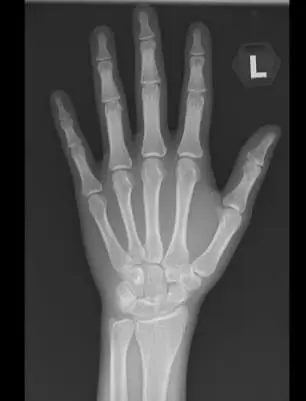

He also conducted an X-ray examination of his left hand to measure the level of his bone maturity.

The X-ray showed that it had reached full maturity and that it was impossible for him to pursue growth hormone treatment.

“I also predicted his adult height and found that it was below average. Unfortunately, it’s too late to do anything about it now,” he wrote.